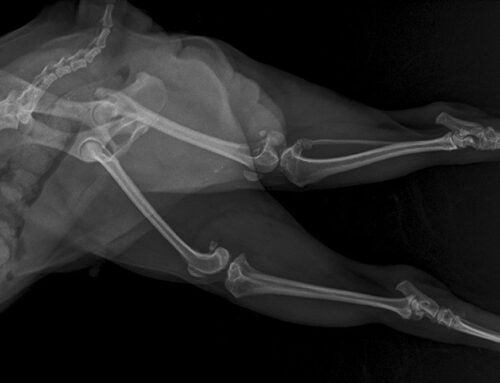

“Brachycephalic” translates quite literally to “short head”. Dogs with shortened skulls have all the same amount of airways structures as a normal dog- just compressed into a much smaller area. This flattened shape narrows nasal passages and often results in a soft palate that’s too long for their head, which then partially blocks airflow. Breeds like Bulldogs, Boston Terriers, Boxers, and Pekingese are predisposed to these challenges.

Breathing problems in flat-faced dogs are often caused by a group of structural airway abnormalities collectively known as brachycephalic obstructive airway syndrome. BOAS is not a single disorder, but a combination of four anatomic problems that work together to restrict airflow and increase breathing effort. These conditions are present from birth, but clinical signs often worsen with age, weight gain, heat exposure, or increased activity.

- Stenotic nares: Narrowed nostrils significantly limit the amount of air that can enter the nose, forcing dogs to breathe through their mouths even at rest. This constant resistance increases airway turbulence, leading to snorting, loud breathing, and reduced exercise tolerance. Over time, the increased effort required to inhale places strain on the rest of the upper airway. Dogs with stenotic nares often show worsening symptoms in warm or humid conditions.

- Elongated soft palate: In many brachycephalic dogs, the soft palate extends too far back into the throat, partially blocking the airway during breathing. As air moves past the excess tissue, it vibrates, creating the characteristic snoring or gagging sounds. During excitement or exercise, the soft palate can obstruct airflow even further, leading to coughing, retching, or collapse. Chronic irritation from abnormal airflow can also cause inflammation that narrows the airway over time.

- Everted laryngeal saccules: These small pockets of tissue near the vocal cords are not a primary defect but develop secondary to long-term breathing resistance. As dogs struggle to inhale against narrowed nostrils and an elongated soft palate, negative pressure pulls the saccules into the airway. This further reduces airflow and increases breathing noise, creating a cycle of progressive obstruction. Once present, everted saccules can significantly worsen respiratory effort and clinical signs.

- Hypoplastic trachea: A hypoplastic trachea is abnormally narrow along its entire length, limiting the amount of air that can reach the lungs. This condition reduces respiratory efficiency and increases the work required for normal breathing. While the trachea itself cannot be surgically widened, recognizing this condition is essential for managing expectations and overall airway health.